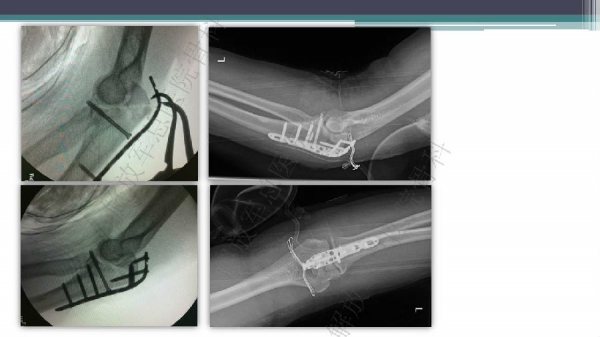

桡骨头、颈骨折手术入路

导语:桡骨骨折是一类临床很常见的骨折类型,大约占成人全部骨折中的15%,随着人口老龄化,高龄患者的发生率亦越来越高。桡骨骨折切开复位手术入路一直以来较为多样化,每种入路亦有其优缺点。在本次幻灯中,解放军总医院骨科的唐佩福教授、陈华教授将与我们分享桡骨头、颈手术手术入路相关经验,精彩内容逐一展现。